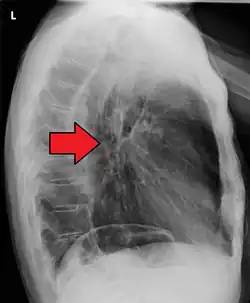

The presence of the tumor may disrupt the normal contractions of the esophagus when swallowing. This can lead to nausea and vomiting, regurgitation of food and coughing.[15] There is also an increased risk of aspiration pneumonia[15] due to food entering the airways through the abnormal connections (fistulas) that may develop between the esophagus and the trachea (windpipe).[14] Early signs of this serious complication may be coughing on drinking or eating.[19] The tumor surface may be fragile and bleed, causing vomiting of blood. Compression of local structures occurs in advanced disease, leading to such problems as upper airway obstruction and superior vena cava syndrome. Hypercalcemia (excess calcium in the blood) may occur.[15]

If the cancer has spread elsewhere, symptoms related to metastatic disease may appear. Common sites of spread include nearby lymph nodes, the liver, lungs and bone.[15] Liver metastasis can cause jaundice and abdominal swelling (ascites). Lung metastasis can cause, among other symptoms, impaired breathing due to excess fluid around the lungs (pleural effusion), and dyspnea (the feelings often associated with impaired breathing).

Additional testing is needed to assess how much the cancer has spread (see § Staging, below). Computed tomography (CT) of the chest, abdomen and pelvis can evaluate whether the cancer has spread to adjacent tissues or distant organs (especially liver and lymph nodes). The sensitivity of a CT scan is limited by its ability to detect masses (e.g. enlarged lymph nodes or involved organs) generally larger than 1 cm.[44][45] Positron emission tomography is also used to estimate the extent of the disease and is regarded as more precise than CT alone.[46] PET/MR as a novel modality has shown promising results in preoperative staging with fair feasibility and good correlation in comparison to PET/CT. It can enhance tissue differentiation with lowering the radiation dose to the patient.[47] Esophageal endoscopic ultrasound can provide staging information regarding the level of tumor invasion, and possible spread to regional lymph nodes.